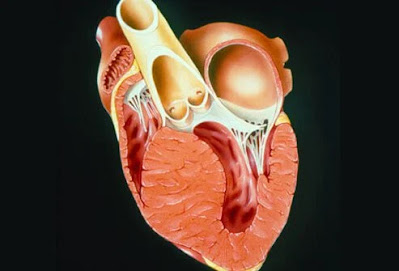

Οι καρδιακές παθήσεις αναφέρονται σε καταστάσεις που αφορούν την καρδιά, τα αγγεία, τους μυς, τις βαλβίδες ή τις εσωτερικές ηλεκτρικές οδούς που είναι υπεύθυνες για τη μυϊκή συστολή.

Οι συνήθεις παθήσεις της καρδιάς περιλαμβάνουν:

Στεφανιαία νόσο

Συγκοπή

Καρδιομυοπάθεια

Νόσος της Καρδιακής βαλβίδας

Αρρυθμίες